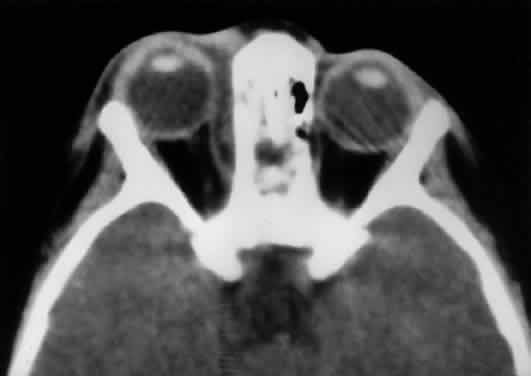

Radiographically, the spaces and foramina of the orbital apex may be considered to lie in three tiers (Fig. 8). The CS is found on the same level as the orbital apex, connecting directly with it via the superior orbital fissure (SOF) to form the middle tier. The inferior tier is formed by the inferior orbital fissure (IOF), which provides direct communication between the orbital apex and the pterygopalatine fossa, a vertically oriented space directly behind the maxillary sinus. Finally, the optic canal has no direct communication with any of the aforementioned spaces and should be considered to lie above the SOF and CS, exiting the orbit in a superomedial course through the body of the sphenoid as the superior tier.26 Orbital apical lesions can therefore gain ready access to the CS and pterygopalatine fossa (Fig. 9). Spread into the cranial vault through the optic canal is usually limited to lesions of the optic nerve (glioma) or nerve sheath (meningioma).

Fig. 8. Coronal CT image (bone window) of the orbital apex in a patient with facial trauma. Note the position of the posterior orbital foramina. The optic canal (A) is always seen in conjunction with the laterally adjacent anterior clinoid process (B) on both axial and coronal views. Slightly lower, the superior orbital fissure (C) communicates with the CS, found directly behind it. The inferior orbital fissure (D) provides communication through the orbital floor with the pterygopalatine fossa.